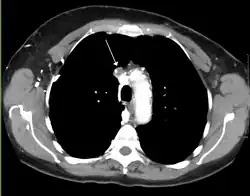

Zespół żyły głównej górnej (ang. superior vena cava syndrome, SVCS) – zespół objawów spowodowanych znacznym utrudnieniem lub zamknięciem przepływu krwi przez żyłę główną górną – krótkiego, szerokiego naczynia doprowadzającego krew obwodową do prawego przedsionka serca[1]. W większości przypadków spowodowany jest zmianami rozrostowymi w obrębie śródpiersia, zazwyczaj jest to rak płuca lub chłoniak nieziarniczy bezpośrednio uciskający lub naciekający ścianę żyły głównej górnej. Obserwuje się również wzrost występowania zespołu spowodowany zwiększoną częstością ingerencji wewnątrznaczyniowych jak np. zakładanie kaniul lub prowadnic, co przyczyniać się może do powstawania zakrzepicy[2]. Innymi przyczynami niezwiązanymi z procesami nowotworowymi mogące powodować zespół mogą być np. tętniaki aorty, infekcje lub zapalenie śródpiersia[3].

W chwili obecnej około 2/3 przypadków spowodowanych jest nowotworem płuc (80% przypadków dotyczy guza prawego płuca) oraz chłoniakami. Może występować również w przebiegu nowotworów tarczycy, grasicy oraz przerzutów do śródpiersia. Inne choroby mogące wywołać SVCS: tętniak aorty, zapalenie naczyń, przetoki tętniczo-żylne, gruźlica, sarkoidoza, kiła, aktynomikoza, grasiczak, zapalenie osierdzia, śluzak przedsionka serca, zakrzepica[6].

Zablokowanie przepływu krwi przez SVC spowodowane jest najczęściej przez ucisk rosnącego guza na ściany naczynia, rzadziej przez bezpośrednie naciekanie ściany i światła żyły z towarzyszącą zakrzepicą.